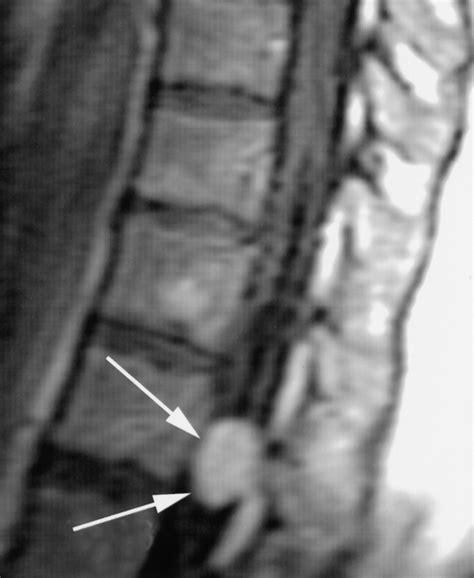

A spinal cord neoplasm is an abnormal growth of cells within or adjacent to the spinal cord. These growths can be classified based on their location: intramedullary (inside the spinal cord substance), extramedullary-intradural (inside the covering of the spinal cord but outside the cord itself), or extradural (outside the spinal cord covering, usually involving the vertebrae). Regardless of the location, these masses exert pressure on the delicate nerve fibers, leading to the clinical manifestations patients experience.

Lumbar (Lower back) Low back pain radiating to the legs, sciatica-like symptoms, bowel/bladder issues.

Once a physician suspects a spinal cord neoplasm based on the described symptoms, they will utilize advanced imaging to confirm the diagnosis. The goal is to identify the size, exact location, and potential nature of the growth. Magnetic Resonance Imaging (MRI) is the gold standard for evaluating spinal cord tumors because it provides high-resolution images of the spinal cord, nerve roots, and surrounding tissues.